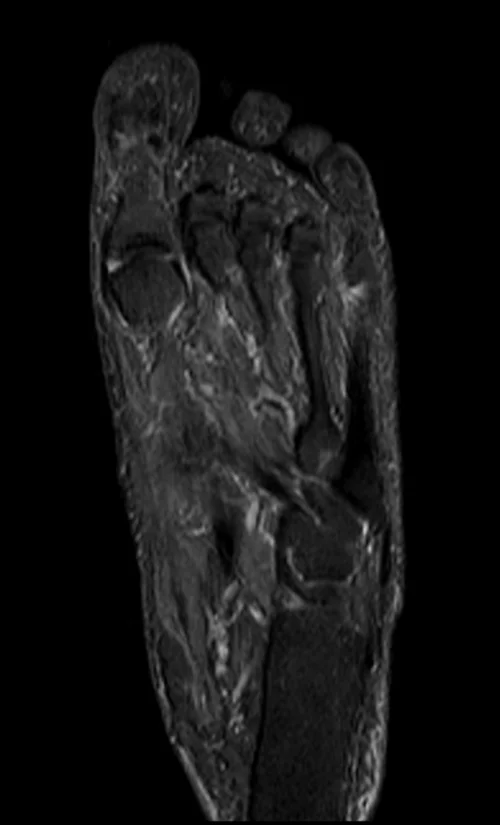

MRI FOOT CORONAL STIR IMAGE 2 - MRI